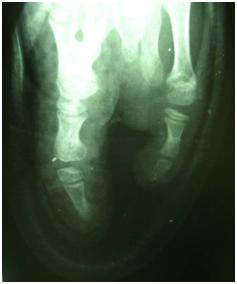

Radiografía con férula y calzado.

SECCIÓN TENDINOSA Y DEL NERVIO CUBITAL DE LA MANO DERECHA

A las tres semanas de la intervención se retiran el yeso y los puntos de sutura y se confecciona férula amovible para poder acudir a rehabilitación.